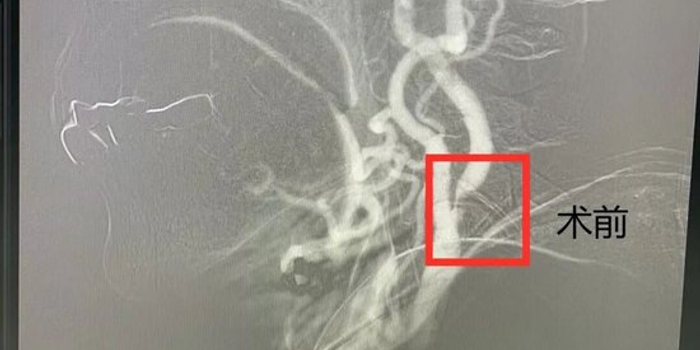

经过充分的术前准备,医疗团队为郭大娘实施了脑血管造影及颈动脉支架植入术。术中,手术团队通过患者大腿根部的股动脉进行穿刺,建立了一个微小的介入通路。在X光透视的精准引导下,将导丝与导管送至右侧颈动脉的狭窄部位,先以球囊进行扩张,随后将一枚支架精准定位并释放。随着支架的张开,原本重度狭窄的血管被成功撑开,大脑的“生命通路”得以重建。